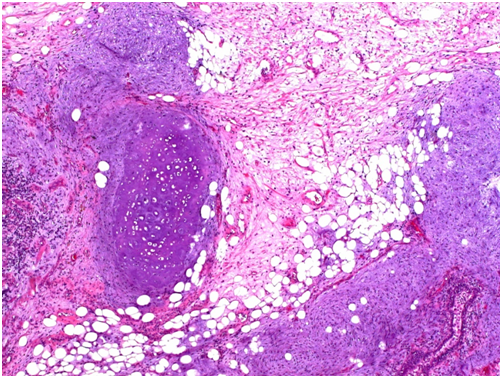

The tumorectomy specimen showed a tumor measuring 14.5x12x11cm and with a weight of 1123g. The lesion was multilobulated on cross sections with some myxoid-appearing areas. Microscopic examination revealed heterogeneity of the tumor. Most of the lesion showed cartilaginous and fatty differentiation with extensive chondroid and chondro-myxoid areas. Also present were narrow slit-like spaces lined by simple columnar and pseudostratified ciliated epithelium. Focally adjacent there was a mild chronic inflammatory infiltrate as well as strands of smooth muscle and focal calcifications. The lesion was well circumscribed and attached to it was a small amount of unremarkable lung tissue. The diagnosis made was chondroid hamartoma or more specifically giant chondroid hamartoma owing to its unusually large size.

Figure 3 Microscopic image showing mature cartilaginous, chondromyxoid and fatty areas, hematoxylin and eosin staining.